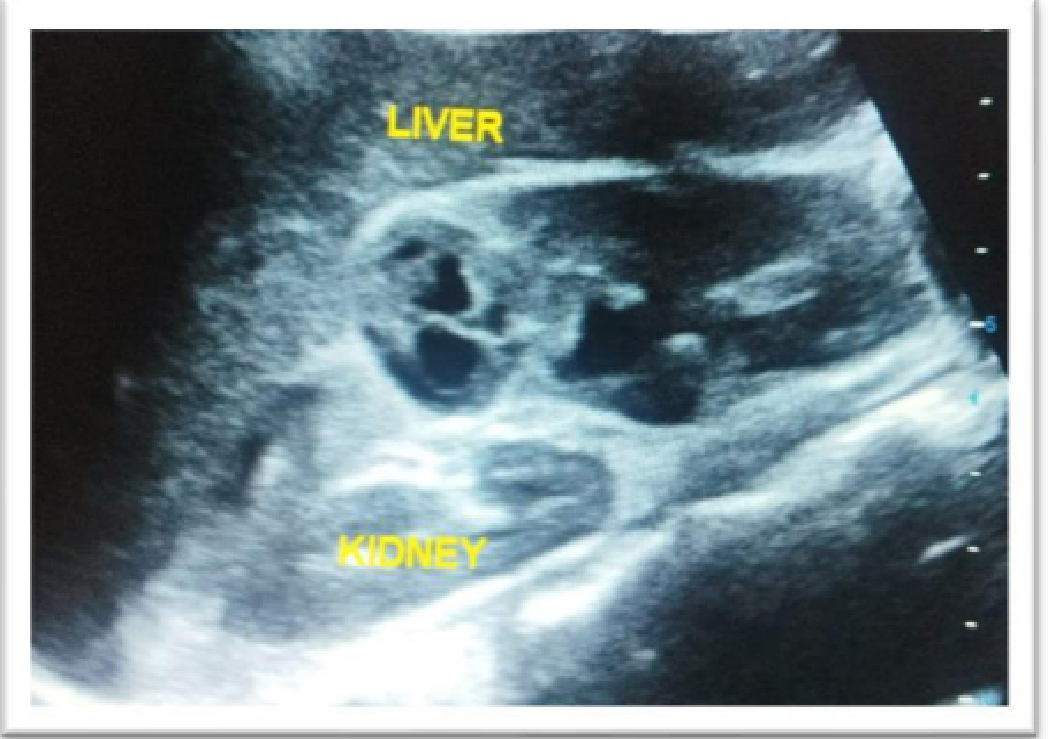

Figure  1:-well-defined  cystic  mass  in Midpole of right   kidneywith   septations   s/o   renal hydatid cyst

Figure 1. -well-defined cystic mass in Midpole of right kidneywith septations s/o renal hydatid cyst